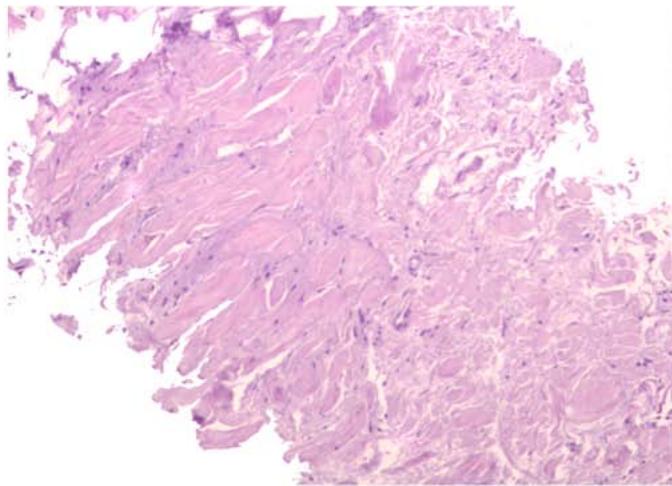

The histological diagnosis is established by the presence of elastic fibers, often fragmented into a collagen matrix. In electronic microscopy: eosinophilic material often contains mature elastic fibers \[23, 28\](Fig. 5).

During additional examination, an ultrasound scan (Fig. 7), chest MSCT (Fig. 8) were performed, which showed no evidence for a lipoma, but there was an elastofibroma of the back detected. For differential diagnosis, a biopsy material was taken followed by a histological examination, the obtained results confirmed the diagnosis of "elastofibromadorsi" (Fig. 9).

B Figure 9: Microslide of elastofibromadorsi. a - Fibro-adipose tissue with collagen and elastic fibers. b - Orcein staining. Elastic fibers are stained brown.